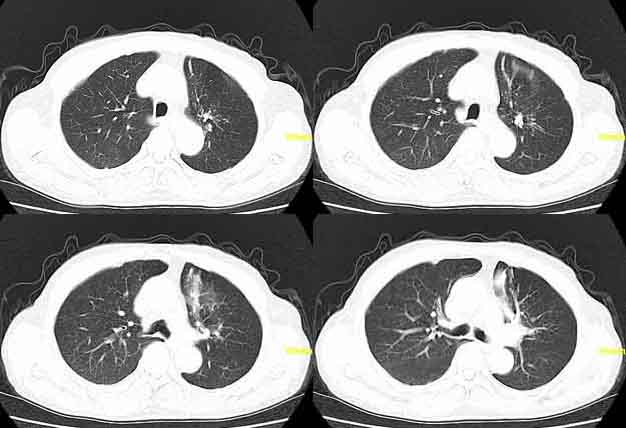

患者,男,76,反复咳血,余病史不详。

左肺上叶相当于前段可见条片状模糊影,,部分呈结节状实变,相应肺门好象显示尚可,上叶支气管阻塞不明显.考虑结核,建议治疗后复查或纤支镜检查

左肺舌叶上舌段见片絮状密度增高影及索条影,索条影与前壁胸膜相连,考虑炎症所致,建议抗炎治疗后复查。

左上叶前段炎症,未见其他异常

要考虑阻塞性肺炎,第二幅肺部图象舌叶似乎有阻塞性肺气肿,建议一月后复查

因为;纵隔窗内见钙化影,病灶呈条索样,并且病人反复咳血,所以考虑结核。